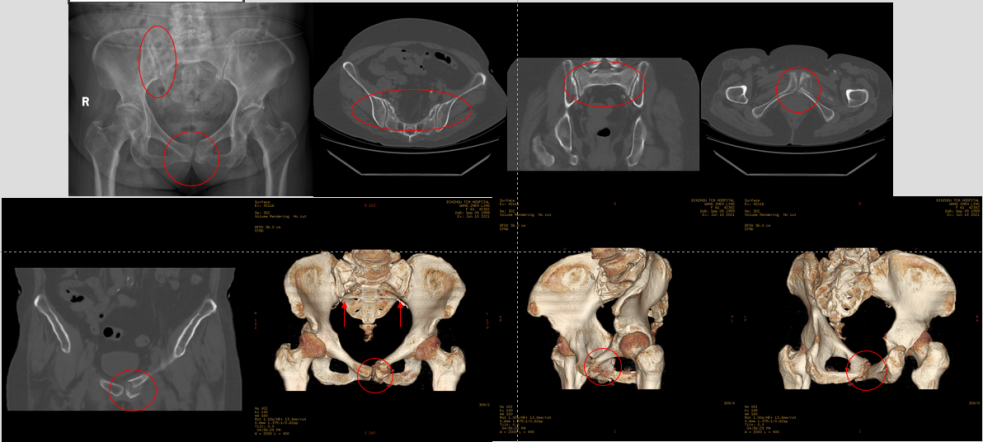

王某某,女 性,61岁,因“腰部及双下肢疼痛2个月”入院,患者2个月前在家中不慎摔倒,臀部着地,逐渐出现腰部及双下肢的疼痛感,行走困难,患者拄着双拐来我院就诊,经过查体检查后,排除腰椎病变,诊断为骨盆骨折(Tile B3型,骨盆后环骨折伴骨盆不稳)。

◆术前影像学资料

在上级专家指导下,科室团队确定了现行给予骨盆内置外架恢复骨盆稳定,再给予经皮骶髂螺钉植入固定后环的手术方案。